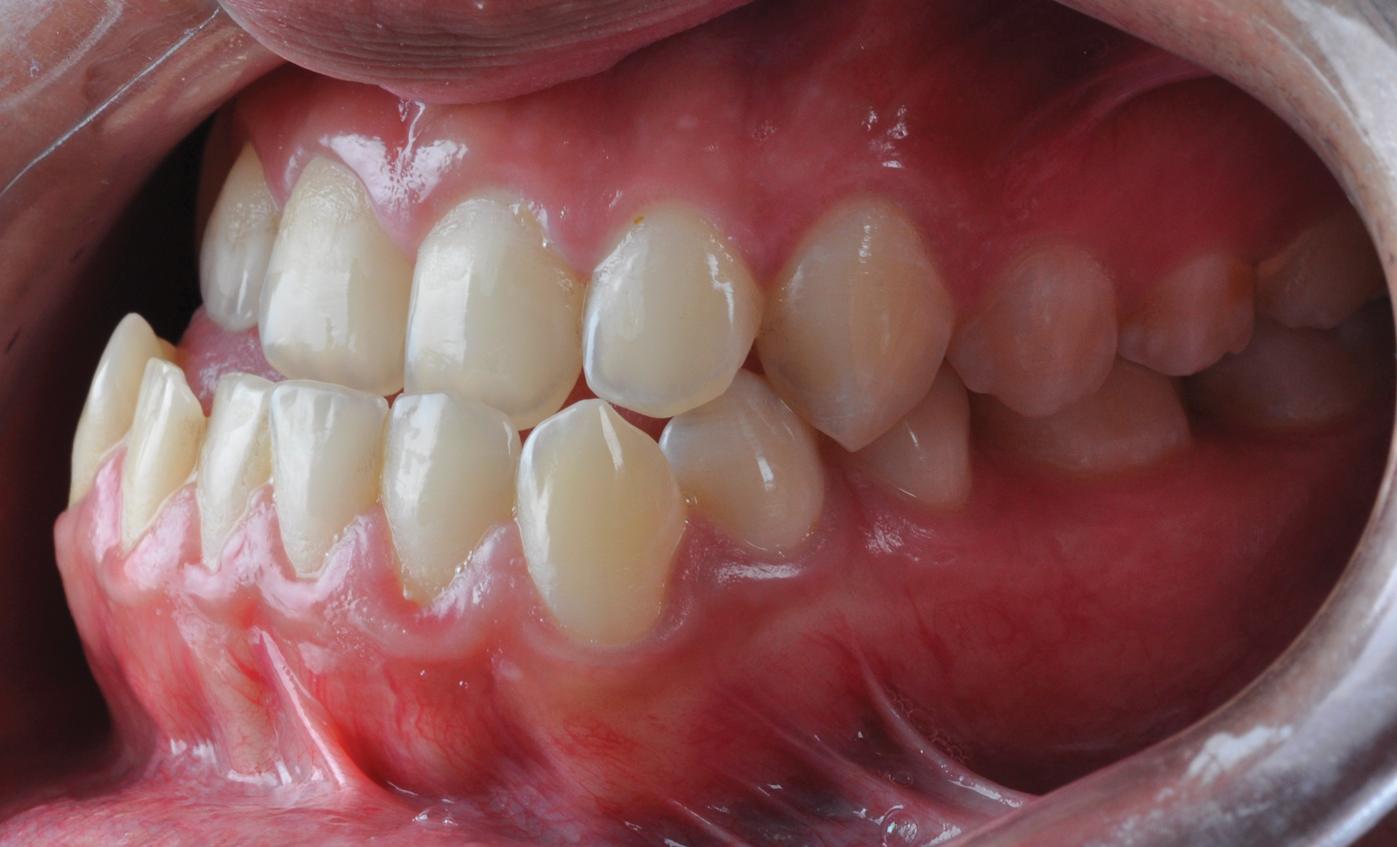

Fig 3. Pretreatment dental views of the patient; right lateral view (Fig 3), frontal view (Fig 4), and left lateral view (Fig 5).

Figure 3